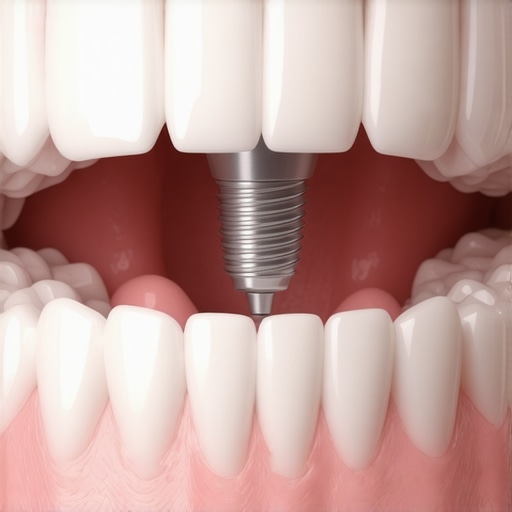

A common myth is that dental implants will last a lifetime without much concern—yet, many fail prematurely due to overlooked factors like bone quality or improper surgical planning. The newest innovations, such as bio-active implants that heal twice as fast, are changing this narrative (study). Another trap is neglecting peri-implantitis risks; poor oral hygiene post-surgery can cause unseen bacterial accumulation, leading to implant loss. Many patients aren’t aware that advanced laser-guided techniques not only speed healing but also mitigate these hidden threats (details). As someone deeply involved in cutting-edge dental care, I recommend consulting professionals who employ these innovations—your long-term oral health depends on it.